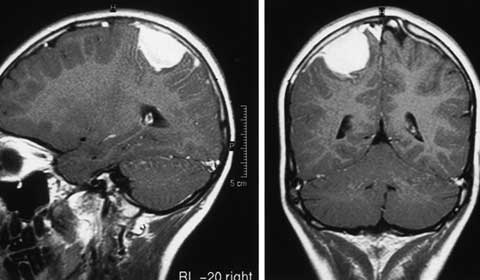

- Chụp cắt lớp vi tính (CT) hoặc cộng hưởng từ (MRI): Đây là hai phương pháp chẩn đoán chính để xác định có tồn tại khối u trong não hay không. CT scan sử dụng tia X để tạo ra hình ảnh của não, trong khi MRI sử dụng từ trường và sóng vô tuyến để tạo ra hình ảnh chi tiết hơn.

Sau khi quyết định điều trị, các bác sĩ sẽ theo dõi tiến triển của bệnh nhân. Theo dõi này có thể bao gồm các xét nghiệm hình ảnh như MRI hoặc CT scan để đánh giá kích thước của u. Nếu u màng não không tăng trưởng hoặc không gây ra triệu chứng, các bác sĩ có thể quyết định không điều trị.